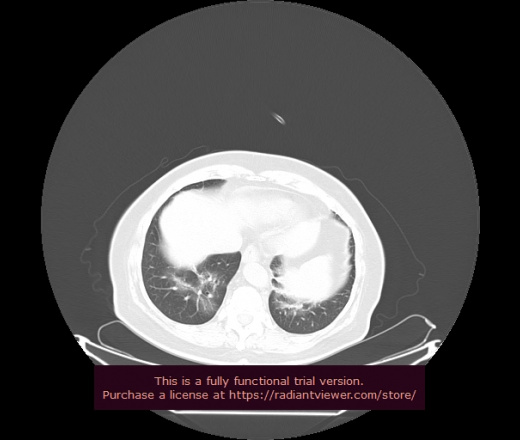

Уважаемые коллеги, если имеется интерес, сможете ли Вы спрогнозировать дальнейшее +-одинаковое течение процесса у 4 данных разных пациентов? Зацепиться где-то можно очень просто, где-то нельзя.